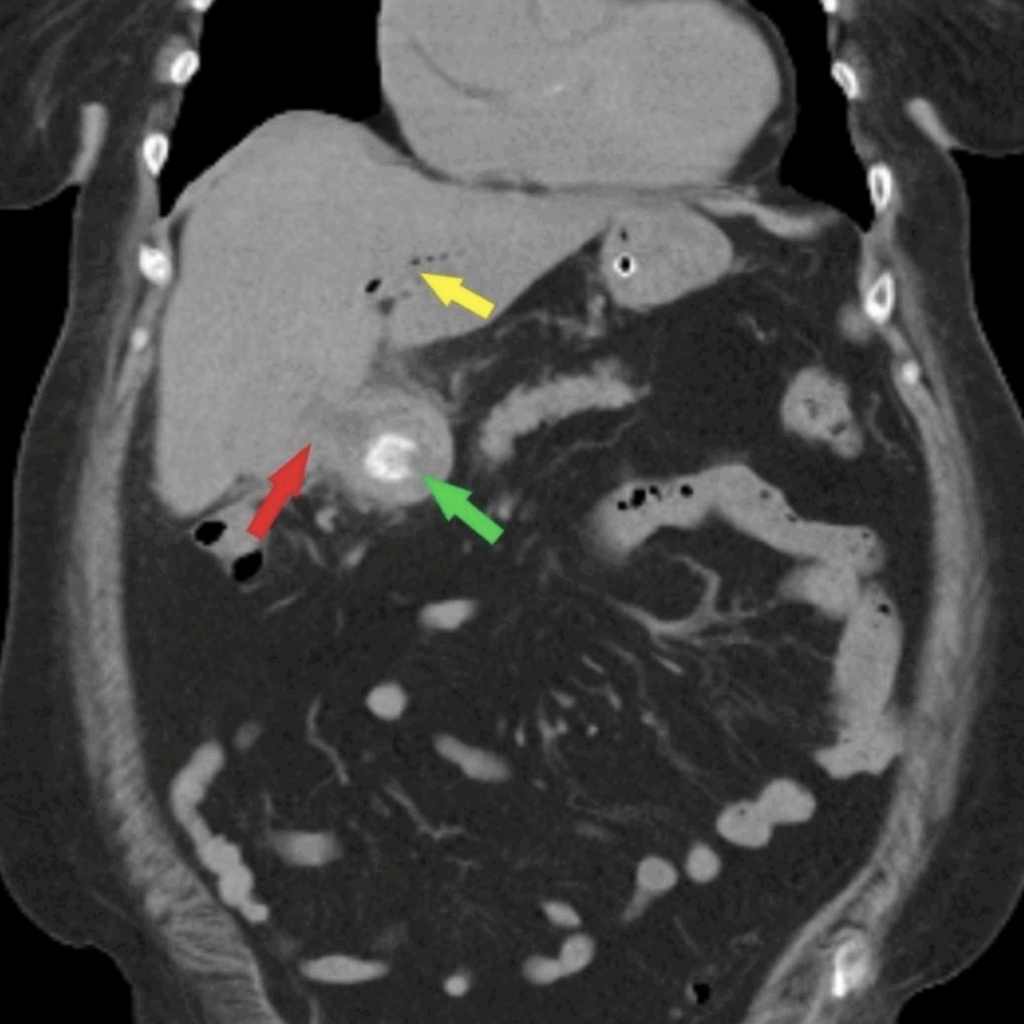

Case 2: Bouveret syndrome with Rigler’s triad: air within the gallbladder (blue arrow), cholecystoenteric fistula (red arrow) with ectopic gallstone in proximal duodenum, and gastric distention (yellow arrow). Radiopaedia